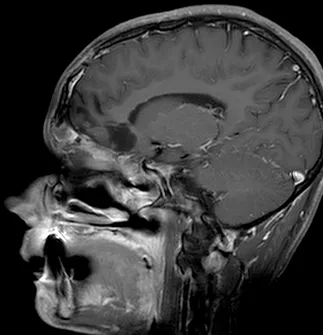

脑部和鼻旁窦计算机断层扫描(CT)和磁共振成像(MRI)扫描显示右侧存在5.5×4.4×5.6厘米肿块,起源于鼻腔、筛窦和蝶窦区域。肿块已侵蚀筛板进入前颅窝。该肿块在CT扫描上未出现钙化(图1),与脑组织等密度,伴有不均匀对比增强。肿块在T1和T2加权MR图像上(图2、3、4)与脑组织等信号,钆增强后显示不均匀强化。注意到周围存在血管源性脑水肿和占位效应。脊柱MRI未见转移证据。

图3:矢状位T1加权钆增强MRI扫描,显示肿瘤团块从鼻旁窦侵蚀进入前颅窝。

Epstein Barr病毒(EBV)原位杂交检测为阴性。电子显微镜显示原始小细胞和较大上皮细胞的混合物,上皮细胞具有形成良好的长细胞间连接。诊断为SNUC。术后患者神经系统状况无变化,头痛症状在术后第十天出院前显著减轻。术后两天进行的磁共振成像显示肿瘤大体全切。患者接受辅助分割放疗,包括对肿瘤床和周围边缘进行的30次分割共6000cGy照射。同时给予顺铂化疗。术后十二个月,患者神经系统状况良好,无影像学或临床证据表明肿瘤复发(图7、8)。

图8:矢状位T1加权钆增强MRI扫描,显示鼻旁窦和前颅窝肿瘤的大体全切。注意额叶无占位效应,肿瘤腔内无对比增强。